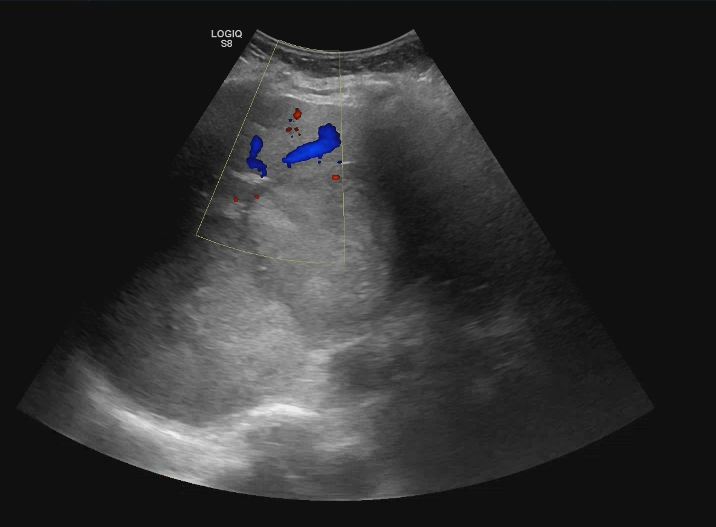

Descripción de los hallazgos ecográficos y las imágenes más relevantes para la resolución del caso

Se realiza ecografía abdominal en la consulta que muestra abundantes lesiones ocupantes de espacio en ambos lóbulos hepáticos, alguna de gran tamaño.Otras pruebas complementarias realizadas (si existen)